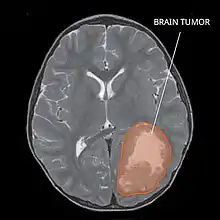

| Primitive neuroectodermal tumor of the central nervous system in a 5-year-old |

Several analysis can be used to determine the presence of the disease. Physical examinations showing papilledema, visual field defects, cranial nerves palsy, dysphasia, and focal neurological deficits are evidences for possible tumor.[2] PNETs can also be spotted through computed tomography (CT) and magnetic resonance imaging (MRI).[2] In images produced by MRIs, an irregular augmentation among a solid mass will indicated the presence of tumor.[3] However, the results of MRIs are usually ambiguous in defining the presence for this specific tumor.[2] In CT scans, the presence of PNETs will be indicated by an elevated density and an increase in volume of the brain.[2] The CT scan can also show calcification,[3] which is present in 41-44% of PNET cases.[2] Since the tumor can be replicated in other parts of the nervous system through the cerebrospinal fluid (CSF), a CSF analysis can also be conducted.[2] A spinal MRI is a fourth type of analysis that is useful in investigating the level of tumor propagation to the spinal cord.[2]

A method for eliminating tumorous mass is surgery, where the best outcome would be total resection, meaning the complete removal of the tumor.[2] Along with the surgery, several measures that contribute to a safe procedure can be taken: urine exams, transfusion, and the constant supervision of arterial pressure.[2] Possible problems that arise from the surgery include hemorrhage, brain edema, and hemiparesis.[2] MRIs are typically done after 1 or 2 days of postoperative in order to inspect the amount of tumor remaining.[2]